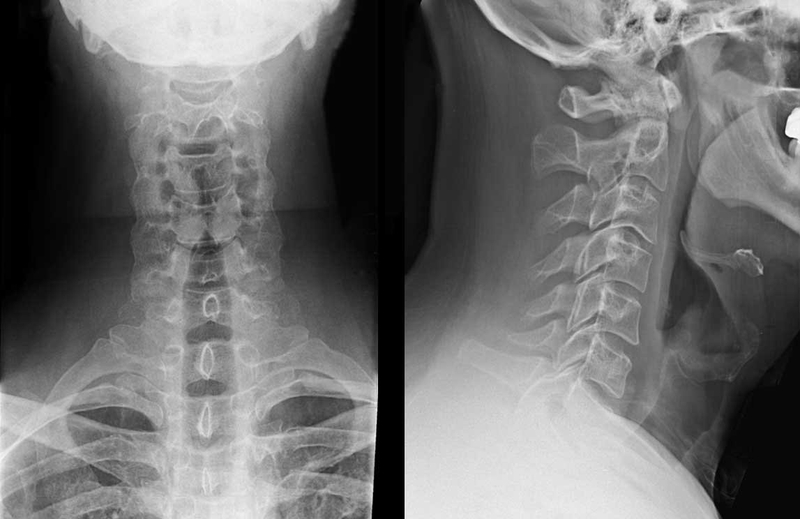

Ngoài ra, có thể sử dụng một số xét nghiệm hình ảnh dưới đây để giúp chẩn đoán hội chứng Brown Sequard:

Chụp X-quang cột sống có giá trị cao trong việc phát hiện vùng cột sống bị ảnh hưởngTrong phần lớn tình huống, việc chẩn đoán hội chứng Brown Sequard được thực hiện dựa vào báo cáo về bệnh sử và chẩn đoán hình ảnh. Hầu hết các trường hợp đều do chấn thương gây ra hội chứng này, điều quan trọng là phải thực hiện các chẩn đoán phân biệt đối với những bệnh tương tự khi không có tiền sử chấn thương. Một số chẩn đoán phân biệt được loại trừ để chẩn đoán hội chứng Brown Sequard là: